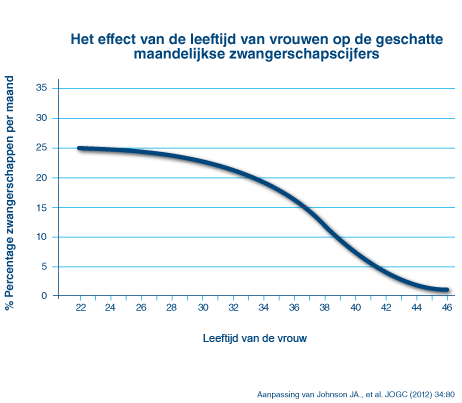

Minder Vruchtbaar Na Je 30ste Dit Is Hoe Het Echt Zit Gezond Ad Nl

Je Maandelijkse Kans Om Zwanger Te Worden Alweer Een Nieuwe Moeder Blog Persoonlijk Mamablog